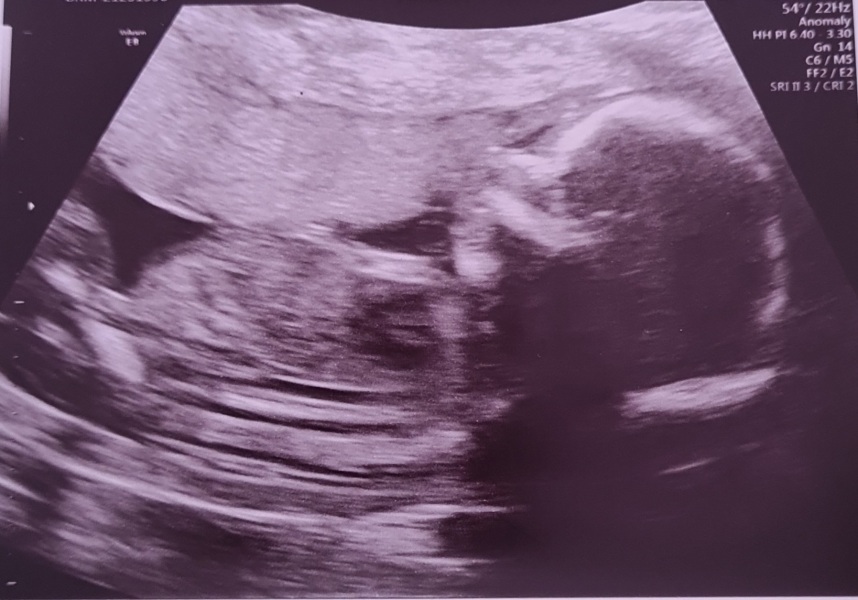

Back from scan. Baby was super chilled, laid back with legs crossed just like their big brother was at this stage. Hopefully stays super chilled when they're here! They confirmed anterior placenta so at least that's why I haven't been feeling strong movements.

We're still firmly team surprise 💛 before I'd even laid down on the bed I'd told the sonographer we didn't want to find out. But comparing to DS scan pics, I think we might be having another boy. So I'm mentally preparing myself to be outnumbered!